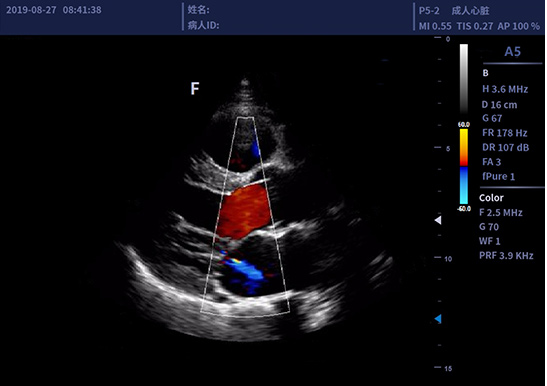

• P5-2/P4-1相控阵探头

适用于心脏、小儿科等

临床超声检查